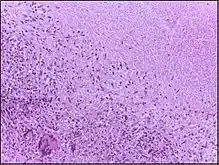

Microscopically, in a Wright's stained peripheral blood smear, a normal lymphocyte has a large, dark-staining nucleus with little to no eosinophilic cytoplasm. In normal situations, the coarse, dense nucleus of a lymphocyte is approximately the size of a red blood cell (about 7 μm in diameter).[13] Some lymphocytes show a clear perinuclear zone (or halo) around the nucleus or could exhibit a small clear zone to one side of the nucleus. Polyribosomes are a prominent feature in the lymphocytes and can be viewed with an electron microscope. The ribosomes are involved in protein synthesis, allowing the generation of large quantities of cytokines and immunoglobulins by these cells.